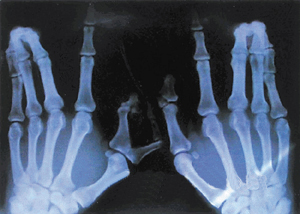

新生儿手指奇特畸形

半年前,在深圳关外打工的一临产妇住进院一家基层医院等待分娩,检查发现这名产妇患有“妊娠高血压综合征”,担心发生分娩危险而将产妇急送到深圳市人民医院产科,在产科的悉心照顾下,产妇顺利分娩了一名男婴。同时医生发现,这名男婴的手指很奇特:两只小手的手指都比正常人多;左手的拇指多指并粘连;双手中指、无名指、小指粘连。从医多年的妇产科医生称,如此特殊的手指畸形,还从未见过。

负责遗传病家系研究的王沙燕博士解释说,正常人每个肢体都是5个手指(趾),如果超过5个手指(趾)即为“多指(趾)”,这种多指现象不算少见;如果出现两个以上的指(趾)粘连现象,即为“并指(趾)”,属于一种 肢体畸形,比较少见。而这个婴儿的特殊在于,两只手同时多指、并指;更出奇的是,这种罕见的现象发生在一个家系,而且连续四代人都有这种“多指并指”现象,可以说罕见的了。